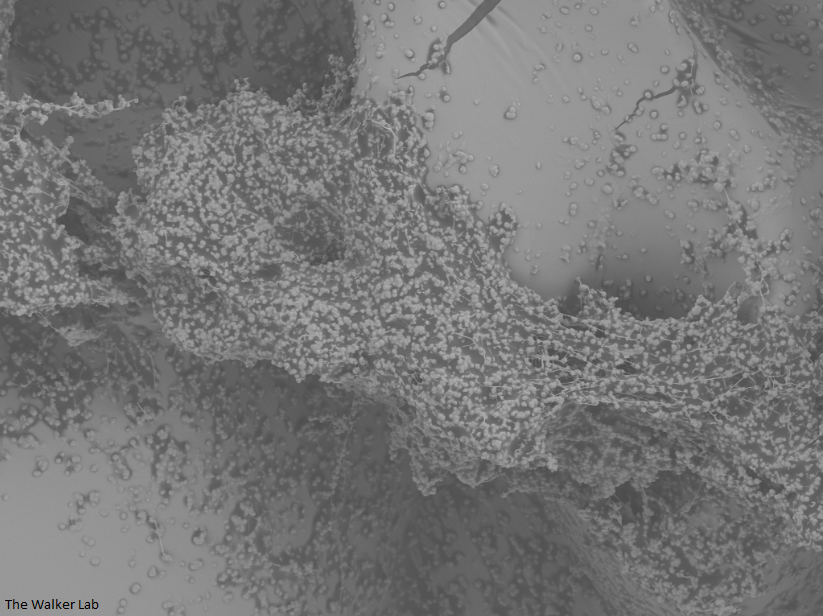

Bladder Epithelial Cells

Host Immune Cells, S. aureus, Pseudomonas

The host inflammation response to the catheter recruits immune cells and wound healing proteins which are deposited on the catheter surface. Atypical pathogens can use these host factors to adhere to the catheter's large surface and create biofilm. Colonization of catheters occurs quicker than expected and develops even in the presence of prophylactic antibiotic therapy. MRSA is just one of the uropathogens that can attach to the altered urinary catheter surface. One host factor deposited on the catheter surface is fibrinogen. We recently discovered that MRSA binds fibrinogen to attach to the catheter surface and form biofilm, which increases antibiotic recalcitrance. Our future studies aim to develop new non-antibiotic strategies that interfere with those interactions to prevent or treat CAUTIs.